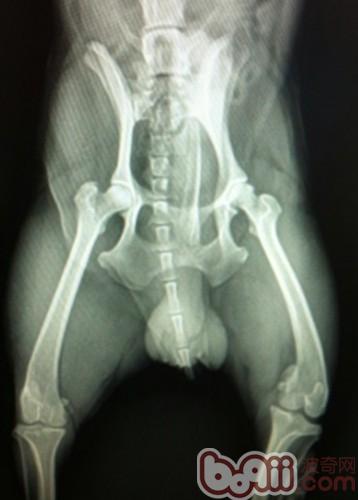

此X光片為數碼片,通過圖中的綠色測量線可發現左側的股骨頭和右側的股骨頭在關節窩里的面積明顯不同,但是由于拍攝此片時患犬未鎮靜麻醉,所以擺位不正,不能作為確診的理由,所以建議還是在患犬肌肉放松的情況下拍片。

6歲田園犬的髖關節,擺位稍有不正,基本在關節窩內二:全髖骨修復術,指用一個假髖臼杯和股骨組件替換退化的髖關節,常用于保守治療無效的年輕成犬,手術成功率很高,但這與實施手術醫生的經驗有很大關系,屬于較為復雜的外科手術,需要有經驗和訓練有序的醫生來實施。